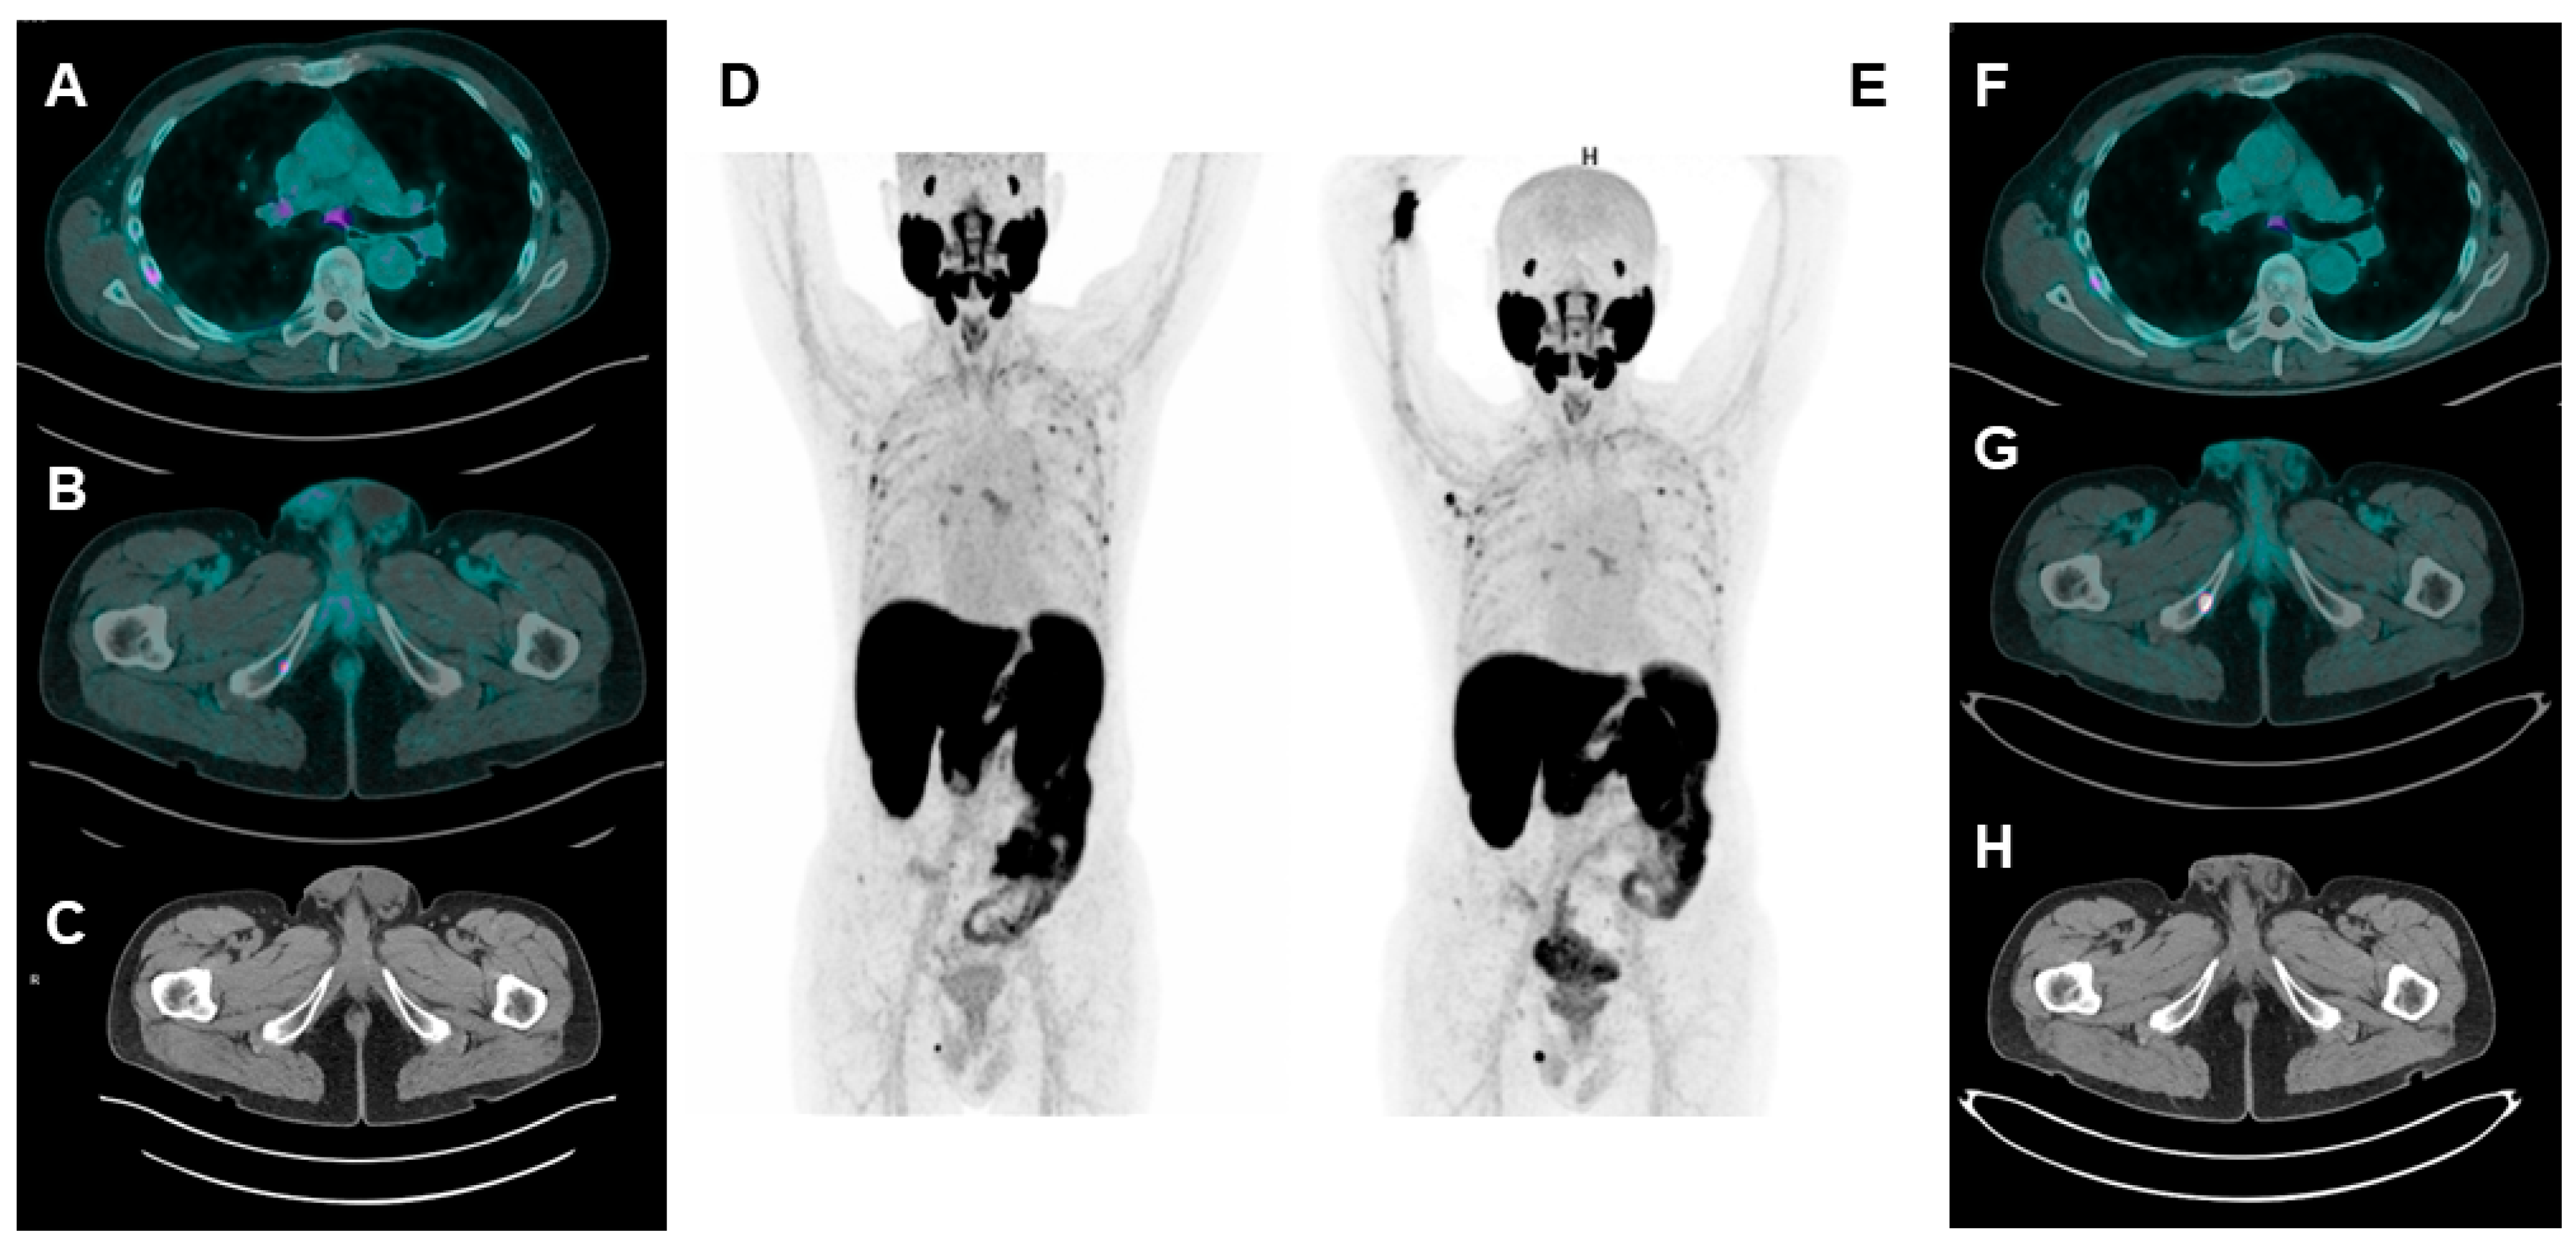

3.3. Dual-Tracer PSMA/18F-FDG: Is It a Must?

- Seifert, R.; Telli, T.; Hadaschik, B.; Fendler, W.P.; Kuo, P.H.; Herrmann, K. Is 18F-FDG PET Needed to Assess 177Lu-PSMA Therapy Eligibility? A VISION-like, Single-Center Analysis. J. Nucl. Med. 2023, 64, 731–737. [Google Scholar] [CrossRef]

- Chen, R.; Wang, Y.; Zhu, Y.; Shi, Y.; Xu, L.; Huang, G.; Liu, J. The Added Value of 18F-FDG PET/CT Compared with 68Ga-PSMA PET/CT in Patients with Castration-Resistant Prostate Cancer. J. Nucl. Med. 2022, 63, 69–75. [Google Scholar] [CrossRef]